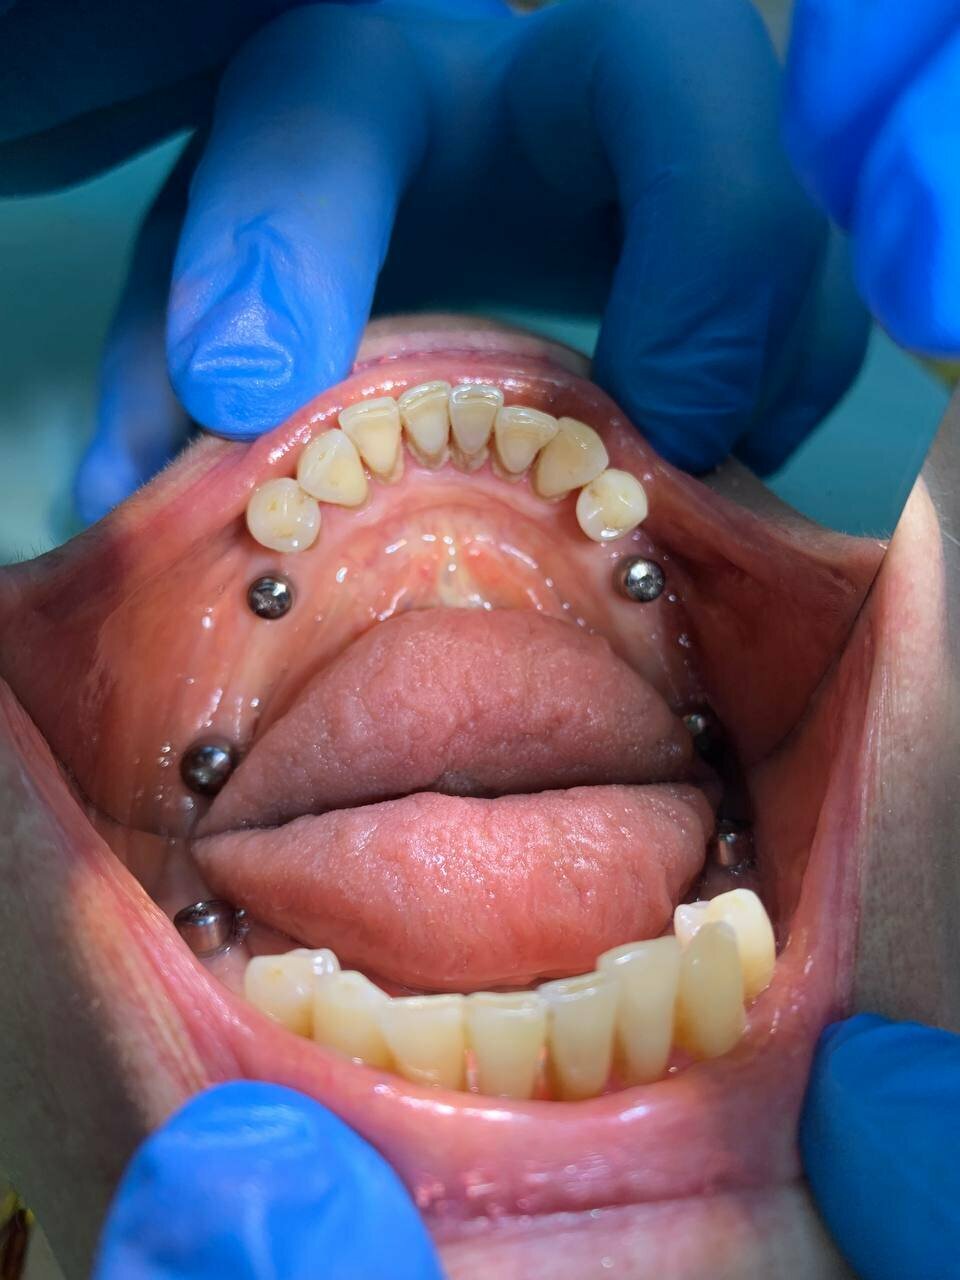

«Сити Дент» охватывает все основные направления стоматологии, включая общую стоматологию, ортодонтию, хирургию, эстетическую и детскую стоматологию. В клинике применяются современные технологии, такие как цифровая стоматология CAD/CAM, лечение под микроскопом, компьютерная томография и рентгенография. Среди дополнительных услуг — имплантология, костная пластика, гнатология, элайнеры, виниры, люминиры, отбеливание, протезирование и челюстно-лицевая хирургия.

Все на высшем уровне, ходили не первый раз и будем продолжать ходить. В первую очередь я обращаю внимание на отношение к человеку, специалисты стоматологии все рассказывают, показывают, объясняют и проводят все необходимые процедуры. В клинике я был на имплантации, со мной контактировали многие доктора, все понравились, работать с ними — просто песня! Команда очень сплоченная!

Лоцманов Алексей Владимирович я считаю опытный и очень хороший врач имплантолог! Отношение к клиентам у него подчеркнуто вежливое! Оборудование современное. Юмор в ходе операции- его сильная сторона. Никаких проблем в ходе имплантации мне 6 имплантов 29.05.2024 г., не возникло. Последствия операции только положительные! Моё лечение продолжается, но самое страшное уже позади. Всем знакомым буду рекомендовать эту клинику.